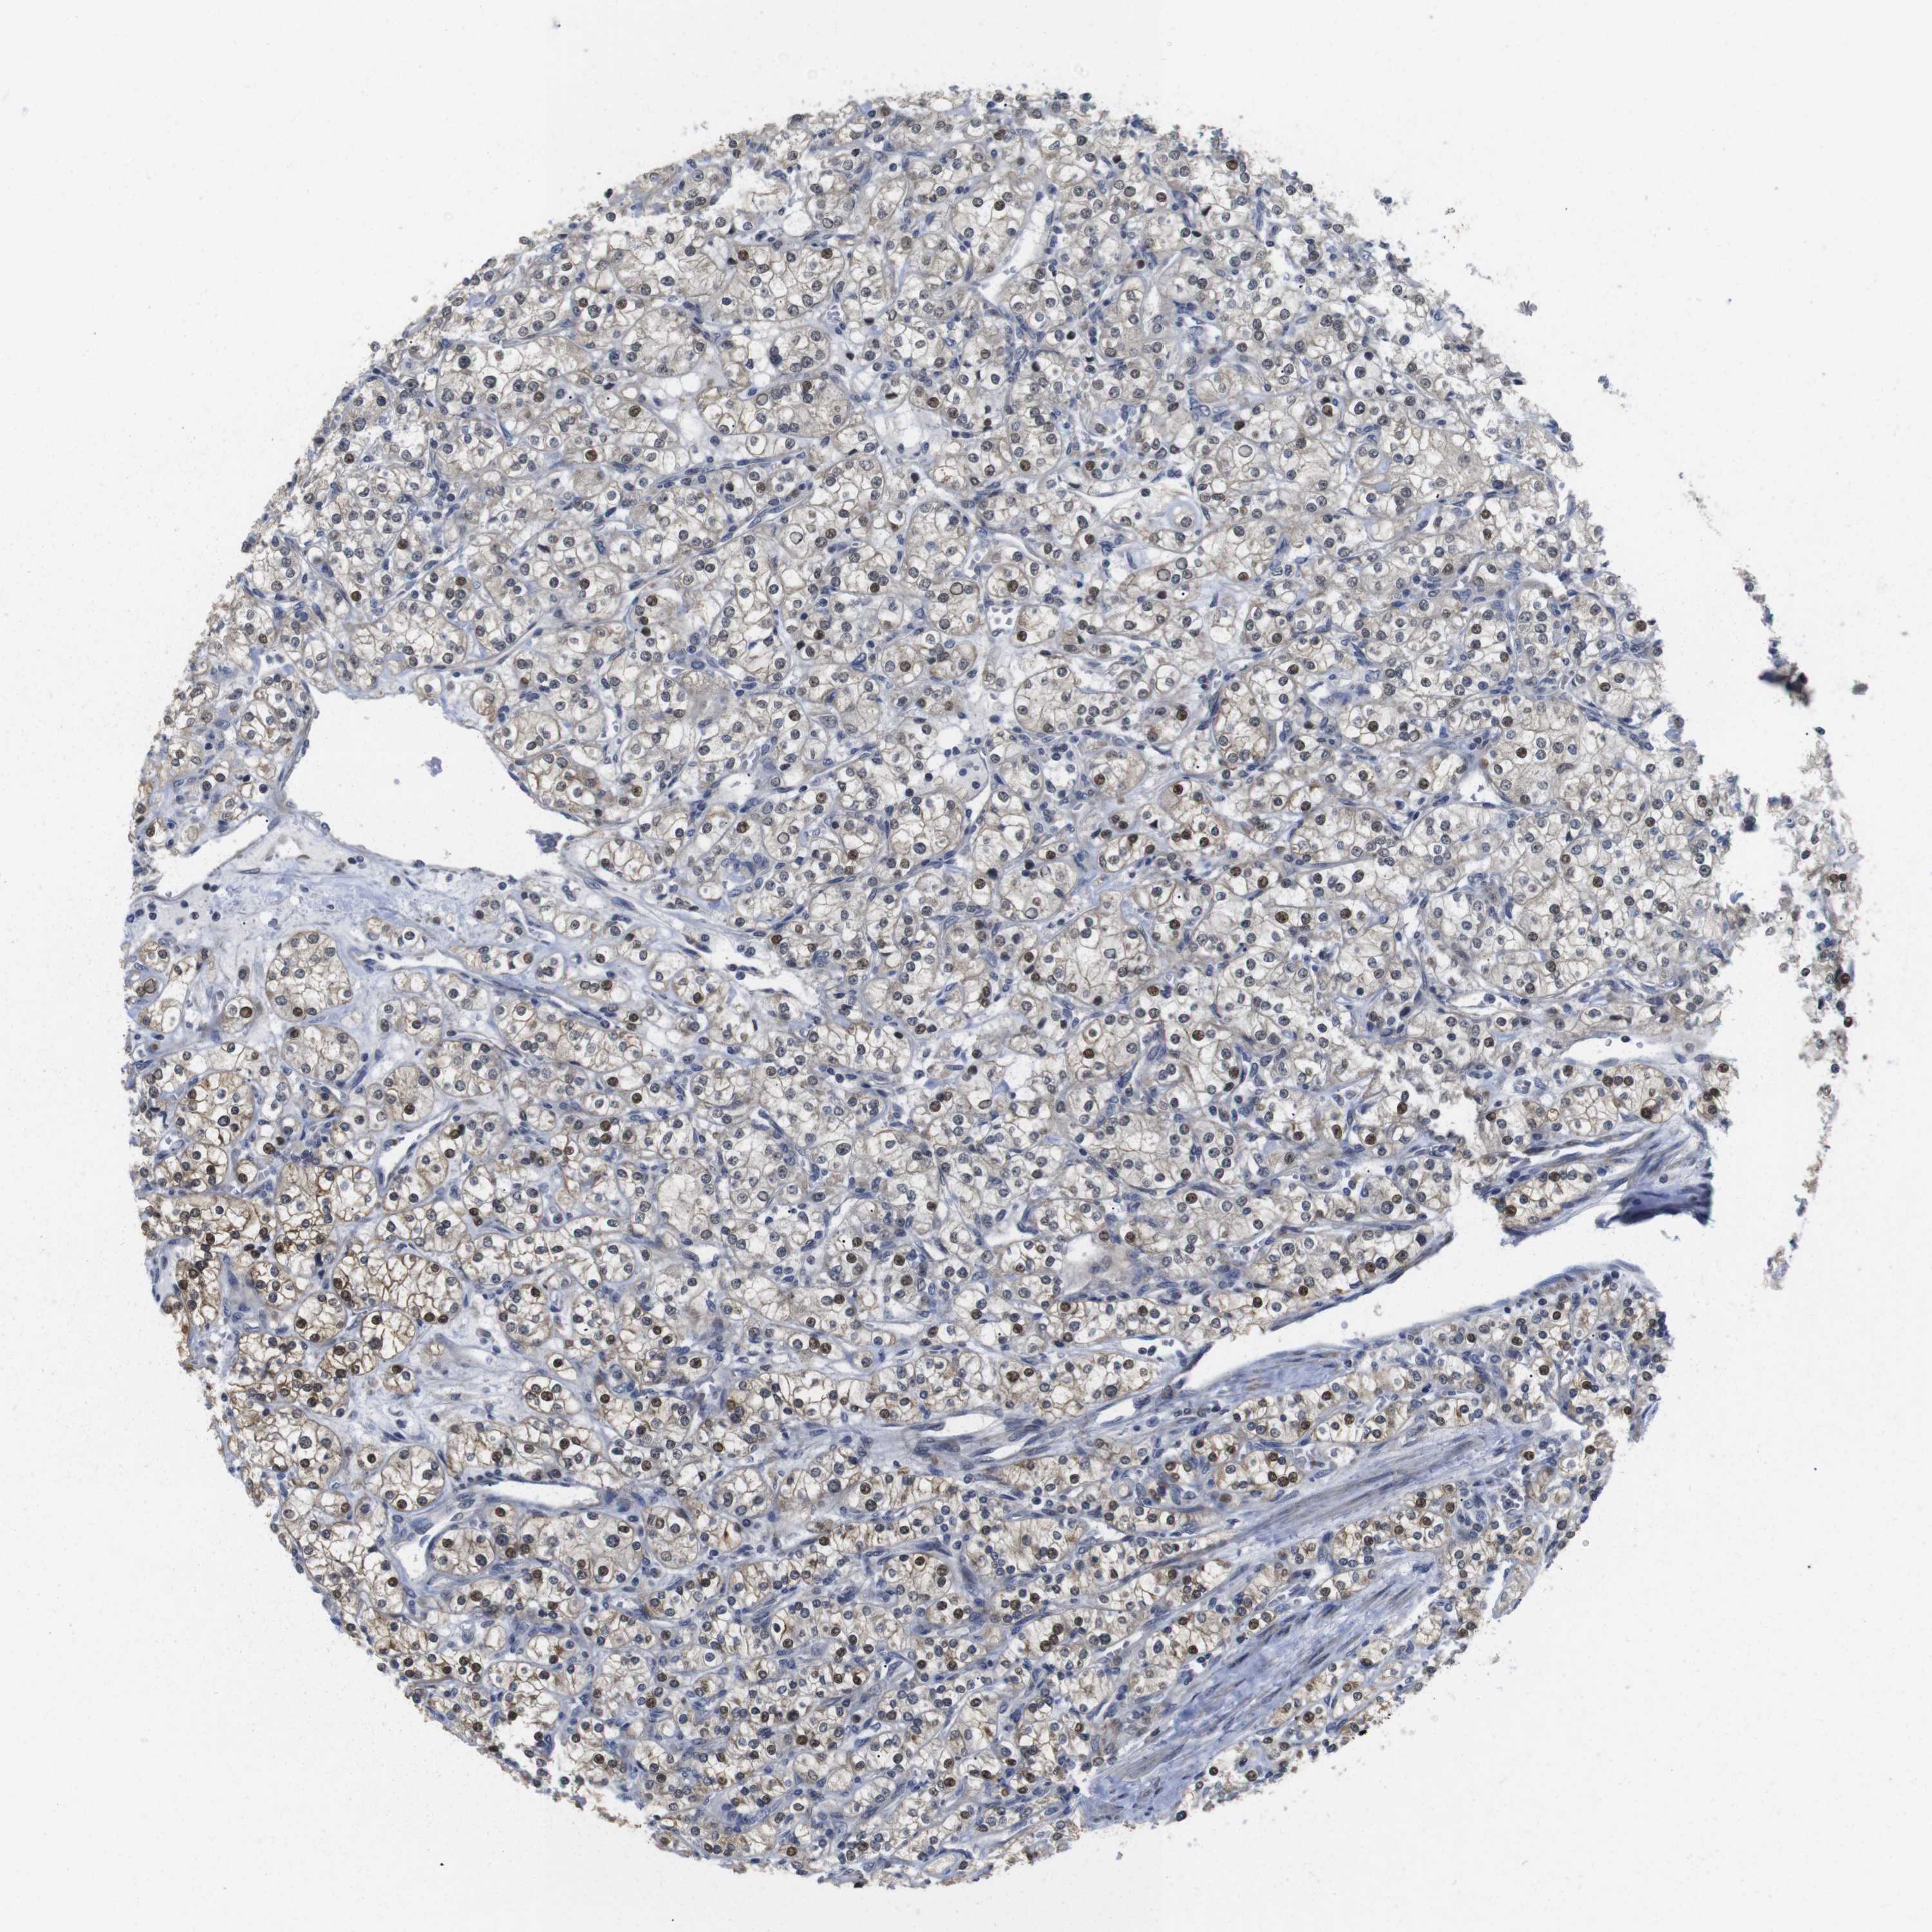

KIDNEY RENAL PAPILLARY CELL CARCINOMA (TCGA) - Interactive survival scatter ploti

The Survival Scatter plot shows the clinical status (i.e. dead or alive) for all individuals in the patient cohort, based on the same data that underlies the corresponding Kaplan-Meier plots. Patients that are alive at last time for follow-up are shown in blue and patients who have died during the study are shown in red.

The x-axis shows the expression levels (FPKM) of the investigated gene in the tumor tissue at the time of diagnosis. The y-axis shows the follow-up time after diagnosis (years). Both axes are complimented with kernel density curves demonstrating the data density over the axes. The top density plot shows the expression levels (FPKM) distribution among dead (red) and alive patients (blue). The right density plot shows the data density of the survived years of dead patients with high and low expression levels respectively, stratified using the cutoff indicated by the vertical dashed line through the Survival Scatter plot. This cutoff is automatically defined based on the FPKM cutoff that minimizes the p-score. The cutoff can be changed by dragging the vertical line or by entering a cutoff value in the square labeled "Current cut-off".

Under the Survival Scatter plot the p-score landscape (black curve; left axis) is shown together with dead median separation (red curve; right axis). Dead median separation is the difference in median mRNA expression between patients who have died with high and low expression, respectively. It is calculated as follows: median FPKM expression of dead patients with high expression - median FPKM expression of dead patients with low expression. This is intended to aid the user in visually exploring custom cutoffs and the associated p-scores and dead median separation.

Individual patient data is displayed and can be filtered by clicking on one or more of the category buttons on the top of the page. Categories describing expression level and patient information include: high, low, alive, dead, female, male and tumor stages. The scale of the x-axis can be toggled between linear and log-scale by clicking on the "x log" button. Mouse-over function shows TCGA ID, patient information and mRNA expression (FPKM) for each patient.

& Survival analysisi

Kaplan-Meier plots summarize results from analysis of correlation between mRNA expression level and patient survival. Patients were divided based on level of expression into one of the two groups "low" (under cut off) or "high" (over cut off). X-axis shows time for survival (years) and y-axis shows the probability of survival, where 1.0 corresponds to 100 percent.

FNTA is potential prognostic, high expression is unfavorable in Kidney Renal Papillary Cell Carcinoma (TCGA)